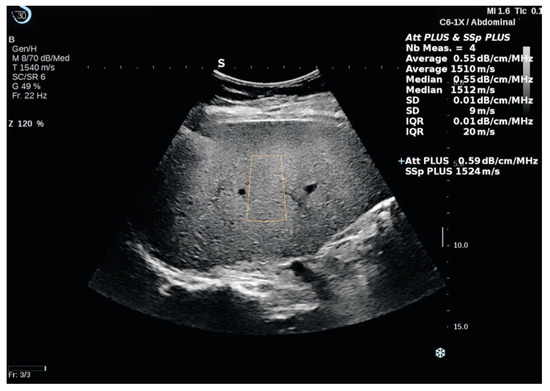

2.4. Attenuation PLUS and Sound Speed PLUS Break to Next Page